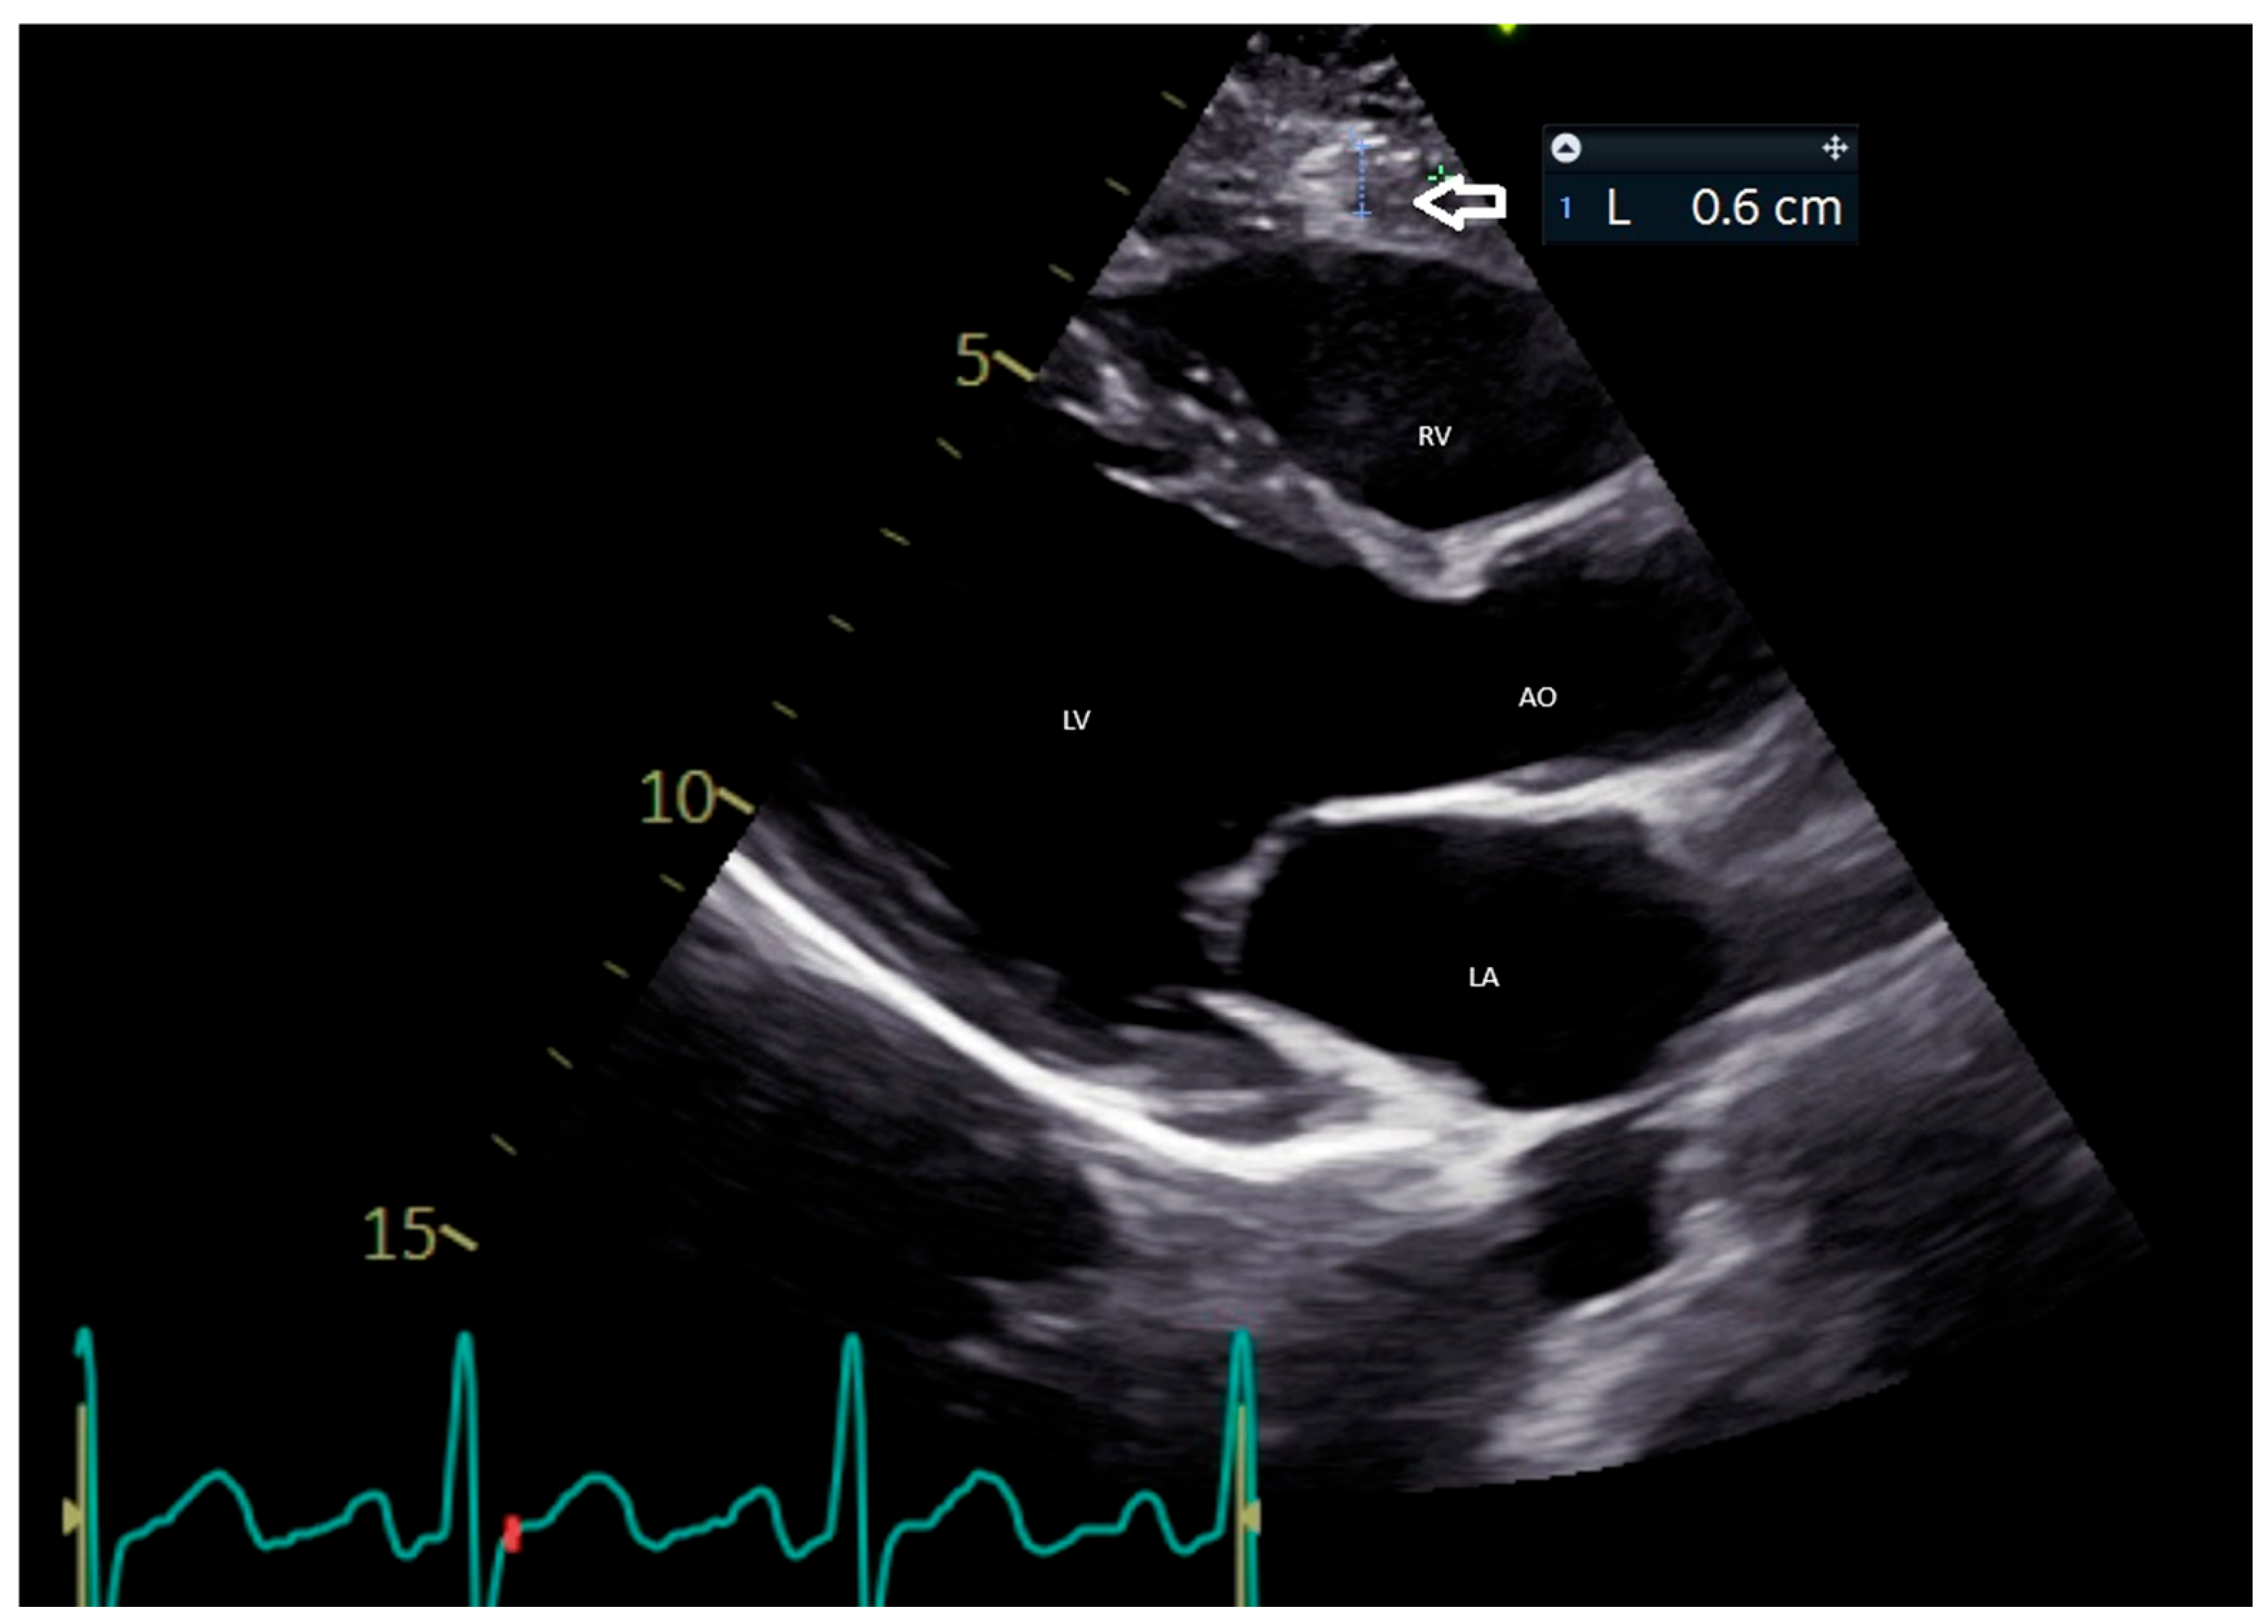

5.1. Echocardiographic Evaluation of EAT

- Iacobellis, G.; Willens, H.J.; Barbaro, G.; Sharma, A.M. Threshold Values of High-Risk Echocardiographic Epicardial Fat Thickness. Obesity 2008, 16, 887–892. [Google Scholar] [CrossRef]

- Natale, F.; Tedesco, M.A.; Mocerino, R.; de Simone, V.; Di Marco, G.M.; Aronne, L.; Credendino, M.; Siniscalchi, C.; Calabrò, P.; Cotrufo, M.; et al. Visceral Adiposity and Arterial Stiffness: Echocardiographic Epicardial Fat Thickness Reflects, Better than Waist Circumference, Carotid Arterial Stiffness in a Large Population of Hypertensives. Eur. J. Echocardiogr. 2009, 10, 549–555. [Google Scholar] [CrossRef]

- Le Jemtel, T.H.; Samson, R.; Ayinapudi, K.; Singh, T.; Oparil, S. Epicardial Adipose Tissue and Cardiovascular Disease. Curr. Hypertens. Rep. 2019, 21, 36. [Google Scholar] [CrossRef] [PubMed]

- Nerlekar, N.; Baey, Y.-W.; Brown, A.J.; Muthalaly, R.G.; Dey, D.; Tamarappoo, B.; Cameron, J.D.; Marwick, T.H.; Wong, D.T. Poor Correlation, Reproducibility, and Agreement Between Volumetric Versus Linear Epicardial Adipose Tissue Measurement: A 3D Computed Tomography Versus 2D Echocardiography Comparison. JACC Cardiovasc. Imaging 2018, 11, 1035–1036. [Google Scholar] [CrossRef]

- Antonini-Canterin, F.; Pellegrinet, M.; Marinigh, R.; Favretto, G. Role of Cardiovascular Ultrasound in the Evaluation of Obese Subjects. J. Cardiovasc. Echogr. 2014, 24, 67–71. [Google Scholar] [CrossRef]